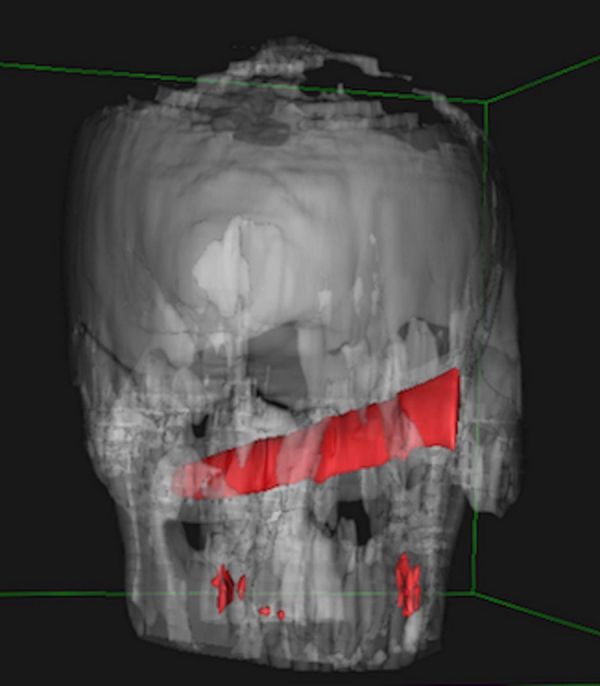

Удар ножом в глаз он получил во время пьяной драки в баре. После этого пострадавший как ни в чем не бывало отправился домой спать. На следующий день мужчине все же пришлось посетить медучреждение. Лезвия он не заметил, однако голова и глаз очень болели. Рентген показал, что нож зашел на 10 см в голову, но не задел ни одной артерии. Врачи даже решили перенести операцию на четыре дня, пока оформлялись необходимые документы.

В результате врачи успешно извлекли лезвие, пациент не пострадал. Теперь мужчина решил пересмотреть свое отношение к дракам с холодным и огнестрельным оружием.